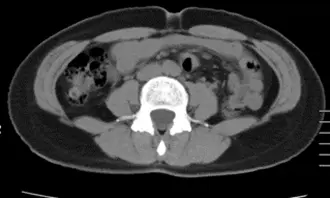

AFTER

OurAge×Webエクラ AFTER

体重 50.3kg  −1.2kg

ウエストサイズ 70.0cm  −8.0cm

体脂肪の量

全体 177.53㎠ +13.87㎠

内臓脂肪 39.53㎠  −0.02㎠

皮下脂肪 138.00㎠  +13.89㎠

「Aさんは、お酒を飲むのが好きなせいか、肝臓に内臓脂肪がついて脂肪肝になっていました。3週間の〈齋藤式満腹やせメソッド〉チャレンジ中は、メソッドの3つの方法を実践しつつ、飲酒については大きく制限をかけていなかったそう。それにもかかわらず、3週間でウエストサイズが8cm、体重が1.2kg落ちたのは、すばらしい結果。写真でもお腹まわりが明らかにすっきりしています。

内臓脂肪の量としては0.02㎠しか落ちていないものの、飲酒をやめていないのに肝機能がよくなっているのがポイント。今まで脂肪肝として代謝が悪くなっていたけれど、〈齋藤式満腹やせメソッド〉を実践することで肝臓の代謝が上がってきたためだと考えられます。これからさらに結果が出てくると思います。

体に入ってきた糖のやりくりをしているのが肝臓なので、肝機能が上がって肝臓がきれいになると、糖代謝も引っ張られて上がってきます。今後は、内臓脂肪がさらに減ってきて、それによって血圧も下がってくるはずです」